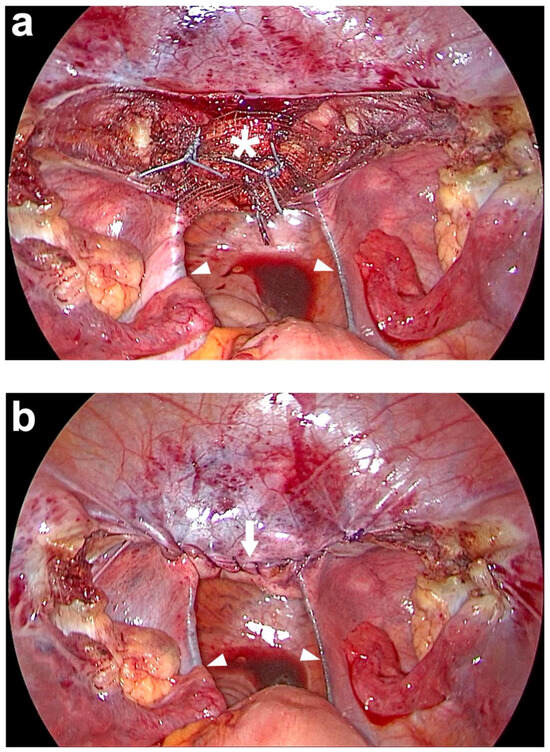

| Anterior fixation of middle part of PVDF structure e (Figure 1) | Sutured to the cut surface of the cervix with 4 interrupted, non-absorbable sutures f. | Sutured to the cut surface of the cervix with 3 interrupted, non-absorbable sutures f (Figure 8a). |

| Peritoneal closure | Closure of peritoneum above cut surface of cervix with running, absorbable suture h. | Closure of peritoneum above cut surface of cervix with running, absorbable suture i (Figure 8b). |